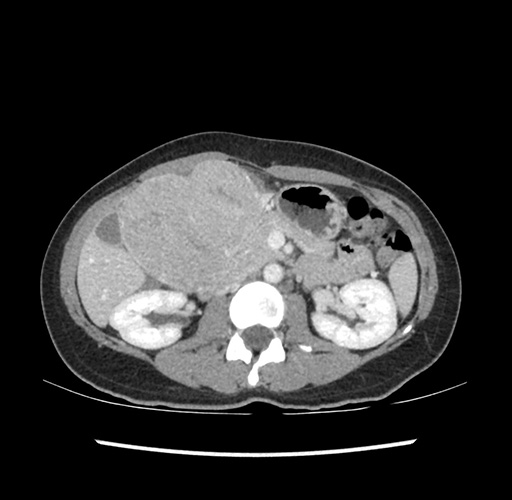

Imaging Analysis

Look through the patient's CT scan to identify any areas of concern for the necessary procedure.

Based on your CT findings, which issue(s) would give reason for "planned slowing down moment(s)" in this case?